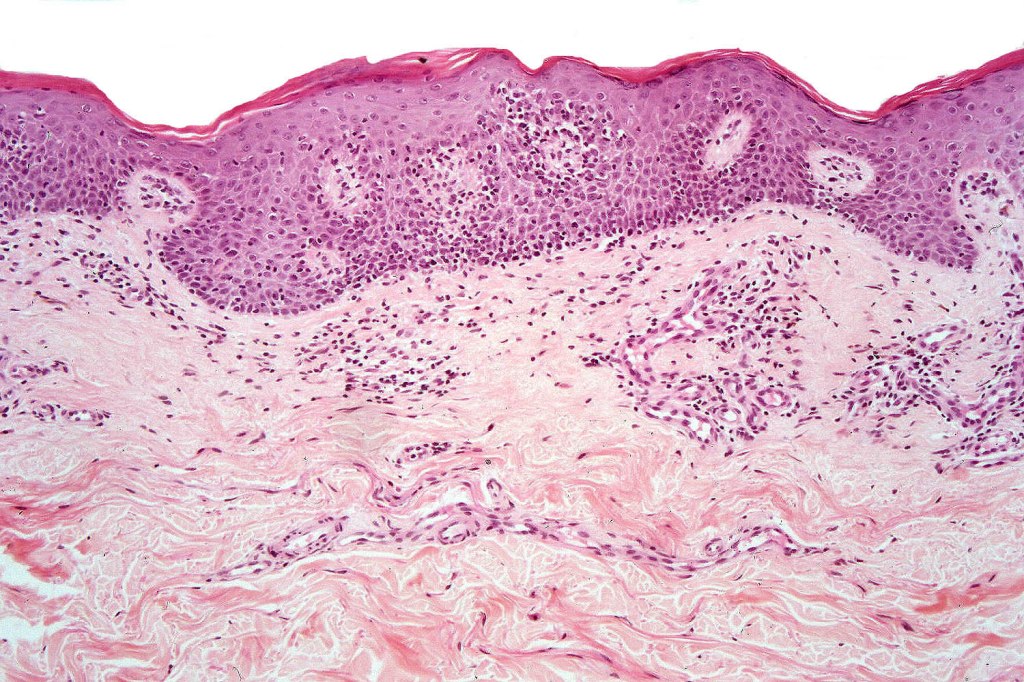

Histological features

The histological hallmark of mycosis fungoides is the presence of large atypical lymphocytes with a convoluted/cerebriform nuclear border (Sézary cells). These may be found at the epidermal-dermal jnuction and as collections within the epidermis (Pautrier microabscess). These are most easily found in plaque stage disease. The epidermal component can be subtle in patch stage disease and is often lost in tumor stage dsease. The classification into patch, plaque & tumor stage disease is less helpful histologically as the features merge from one to the other. It is all a matter of degree.

Patch stage disease

•Changes can be subtle & dependent on clinicopathological correlation; in many patients sequential biopsies over many months may be necessary to establish the diagnosis.

•Mild hyperkeratosis & focal parakeratosis, acanthosis, epidermal atrophy or of normal thickness

•Superficial dermal lymphocytic infiltrate containing variable numbers of Sézary cells with atypical, irregular, hyperchromatic nuclei surrounded by a halo; these can be very few in number and dependant on viewing multiple levels

•Palisading of atypical lymphocytes along the epidermal-dermal border

•Coarse collagen bundles in the papillary dermis can be a feature but this is not as marked as seen in plaque disease

Plaque Stage Disease

•Compact hyperkeratosis & patchy parakeratosis

•Acanthosis

•Psoriasiform hyperplasia common

•Coarse collagen bundles in papillary dermis

•Superficial band-like dermal infiltrate of atypical lymphocytes, eosinophils, plasma cells & histiocytes